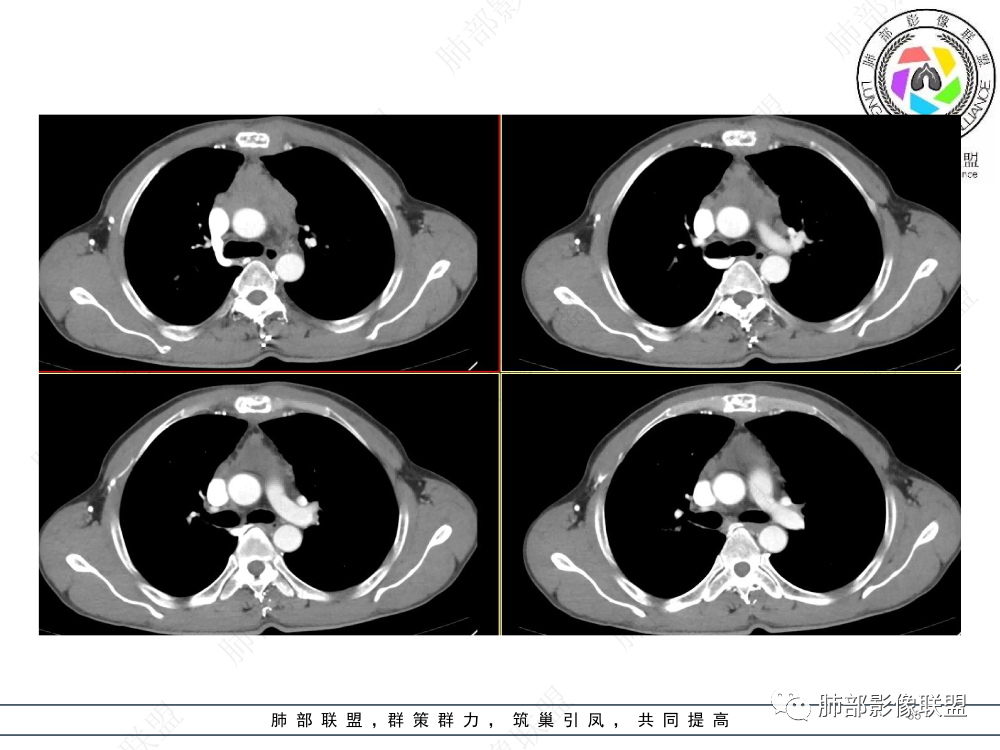

1.临床资料:中老年男性,病史较长-8个月,主诉胸痛,实验室资料:乳酸脱氢酶(LDH)升高。

2.影像表现:前上纵隔较大肿块,密度不均,形态不规则,边界不清,有结节样突起,脂肪间隙显示不清。病灶侵犯左无名静脉及上腔静脉,其中左无名静脉闭塞(胸背部侧支循环明显,亦表明回流受阻)。增强后轻中度不均强化。坏死边界欠清晰。可见心包积液,提示心包受侵犯。右侧上叶及纵隔胸膜下结节影,疑胸膜肺转移可能。胸骨柄后缘皮质不完整,疑骨质破坏(未提供骨窗及矢状位图像)。左锁骨上可见肿大淋巴结。